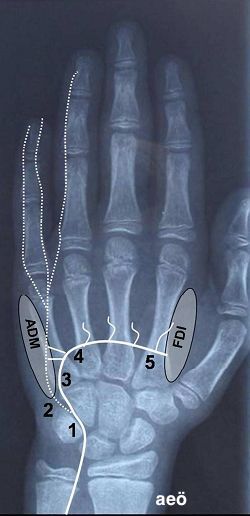

Şekil

4b.

Bilek ve distalinde ulnar sinirin innervasyonları

ve olası tutulum lokalizasyonları